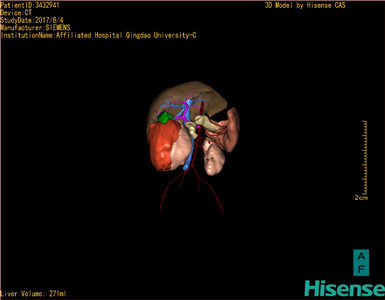

通过调节窗宽窗位调整CT序号,对肿瘤,肝实质,胆囊,下腔静脉,肿瘤,肝动脉、门静脉及肝静脉等进行三维重建;系统自动计算肿瘤体积和肝脏体积。

模拟手术操作,自动计算切除肿瘤体积。肝脏体积为271ml,通过术前模拟手术,精准判断手术可行性。

术前三维重建:

重建图片